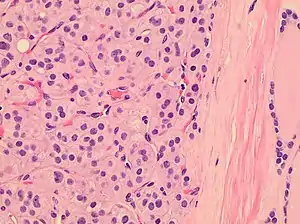

Histopathology of a Hürthle cell adenoma

Hürthle cells are characterized as enlarged epithelial cells. These cells, when stained with hematoxylin-eosin show as pink. This is due to the abundant mitochondria and granular eosinophilic matter within the cells' cytoplasm. These cells are often found in the thyroid. The thyroid is a butterfly-shaped organ, responsible for producing various hormones for metabolism. These cells are often benign, but they can be malignant and metastasize. Hürthle cells are resistant to radiation, but can be treated using radioactive iodine treatment.[4]